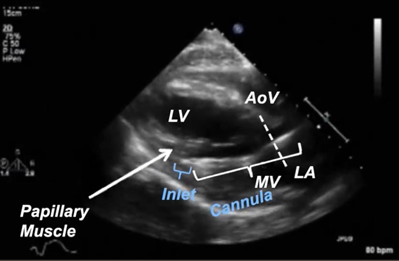

On imaging, the Impella catheter appears as a bright linear echogenic structure crossing the aortic valve. The inlet is typically visualized just apical to the mitral valve plane and often displays a “teardrop sign”—an echolucent space representing blood being drawn into the pump.² The outlet should be in the proximal ascending aorta, not retracting into the valve or extending excessively. The pigtail tip (for Impella 2.5 and CP), visible as a curled loop extending toward the apex, helps reduce myocardial trauma and aids device orientation. Color doppler may reveal continuous flow from the LV to the aorta through the device when the device is properly placed and functioning. Figure 1 shows an example of incorrect positioning, as the inlet is located in the LV myocardium, while Figure 2 demonstrates the correct positioning of the Impella. The inlet positioning should be approximately 3.5–4 cm from the aortic annulus for Impella CP and 5.0, and 5 cm from the aortic annulus for the Imeplla 5.5.²

Figure 1: Improper Impella Placement. This figure shows the impella is advanced too far into the LV cavity, which can cause obstruction to blood flow in the inlet of the impella device.

Figure 2: Proper Impella Placement. This figure shows correct placement of the impella device, with the inlet in the mid LV cavity approximately 3.5cm from the aortic valve annulus.